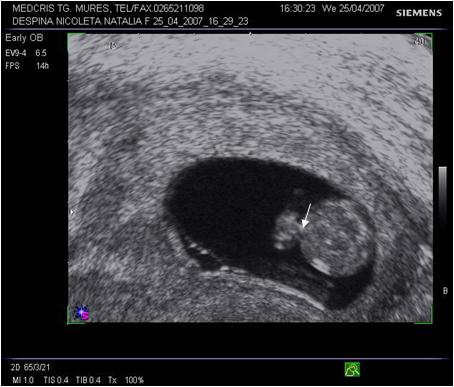

Fig. nr.129 Masurarea pliului nuchal la o marire corespunzatoare

Masurarea NT egala sau peste 3 mm este considerata anormala. Riscul defectelor cromozomiale creste marcat in functie de marimea NT si de varsta mamei, necesitand punctie biopsie de vilozitati choriale sau amniocenteza.

Cea mai buna metoda de screening [18] ramane asocierea varstei materne, masurarea translucentei nuchale si nivelul seric matern de HCG β- human chorionic gonadotropin si PAPP-A (Pregnancy associated plasma protein- A) la 11 - 14 sapt gestationale ( dublu test ). Detectarea defectelor cromozomiale este in jur de 90%, cu ajutorul unui soft ce integreaza aceste date si efectueaza calculul riscului relativ.